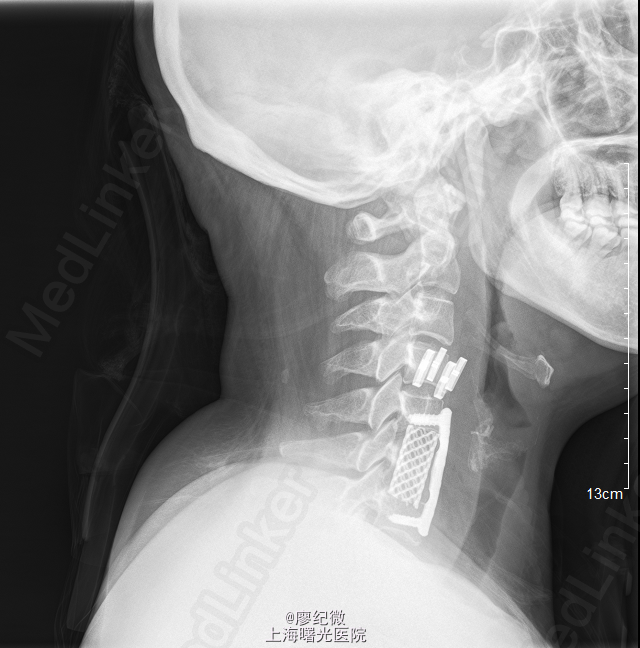

初步诊断:颈椎病. 处理: 全麻麻醉下行“[颈椎]颈椎前路减压融合内固定术”. 作右颈前上斜切口长约6cm,逐层切开皮肤、皮下组织、颈阔肌,自胸锁乳突肌内侧钝性分离,分离直达颈椎前方。经C形臂影像增强器透视确定C6椎体,剥离椎前筋膜和前纵韧带,显露椎体前方,于C7、C5椎体上各置入撑开螺钉1枚,撑开器适当撑开,彻底清除C5/6、C6/7椎间盘,减压彻底后,予以冲洗。取合适大小钛网植入,前方放置一块钢板,C7、C5椎体各攻入两枚螺钉,并予以自锁。经C形臂影像增强器透视位置理想,螺钉长度合适。